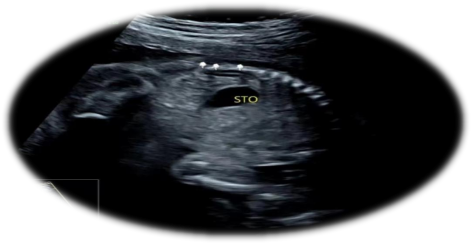

单侧肾缺如的超声表现:

1.一侧肾脏未探及

2.肾上腺平卧征

超声科医生在诊断单侧肾缺如时都非常谨慎,需要非常仔细地检查腹腔内尤其是盆腔内有无异位肾存在,才高度怀疑单侧肾缺如。